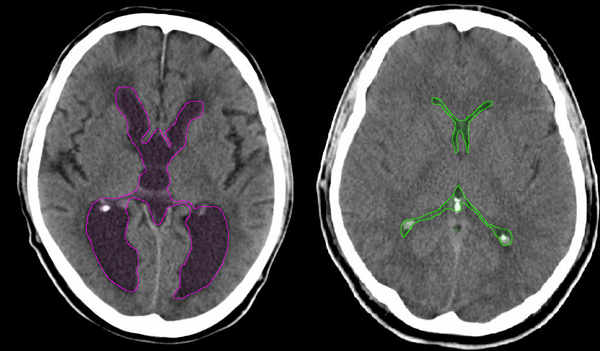

Αξονική τομογραφία ασθενούς με υδροκέφαλο αριστερά, με διάταση του κοιλιακού συστήματος (κόκκινο περίγραμμα). Σύγκριση με φυσιολογικό κοιλιακό σύστημα δεξιά (πράσινο περίγραμμα). |